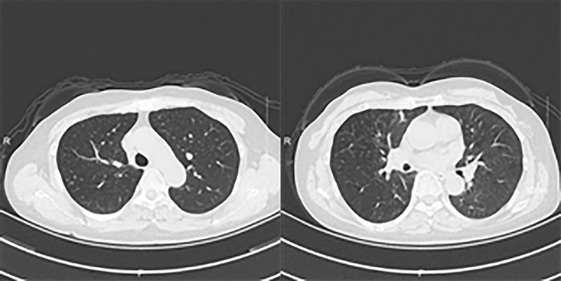

ct显示双肺支气管壁增厚伴分泌物,右肺上叶多发小结节,两肺少许纤维灶